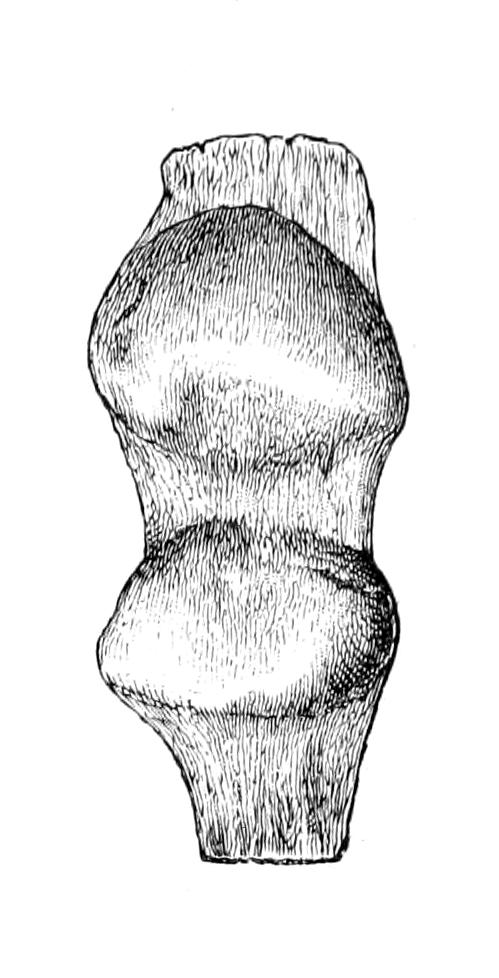

Fig. 1

Congenital hypertrophy: gigantism of both lower extremities. (Case of Dr. Graefe [Sandusky].)